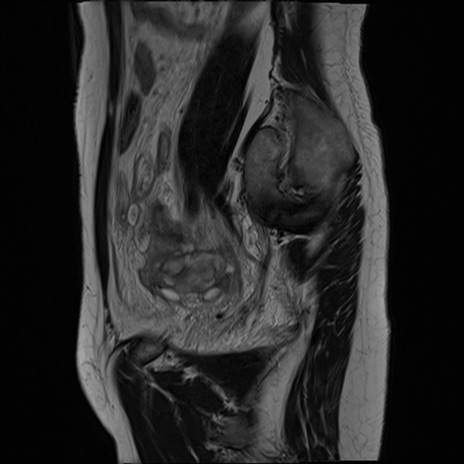

症例39 T2WI(矢状断像)

MRI(4日後)